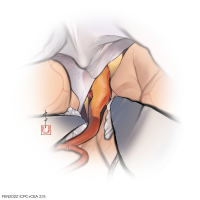

FEN2022シリーズ